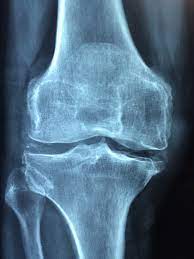

② 수술적 치료법

- 관절 연골이 많이 닳고 손상이 심한 환자에게 적용

- 인공관절 수술, 교정 절골술, 관절 내시경 등이 있음

- 보존적 치료에도 불구하고 통증‧기능장애가 계속 악화하면 고려